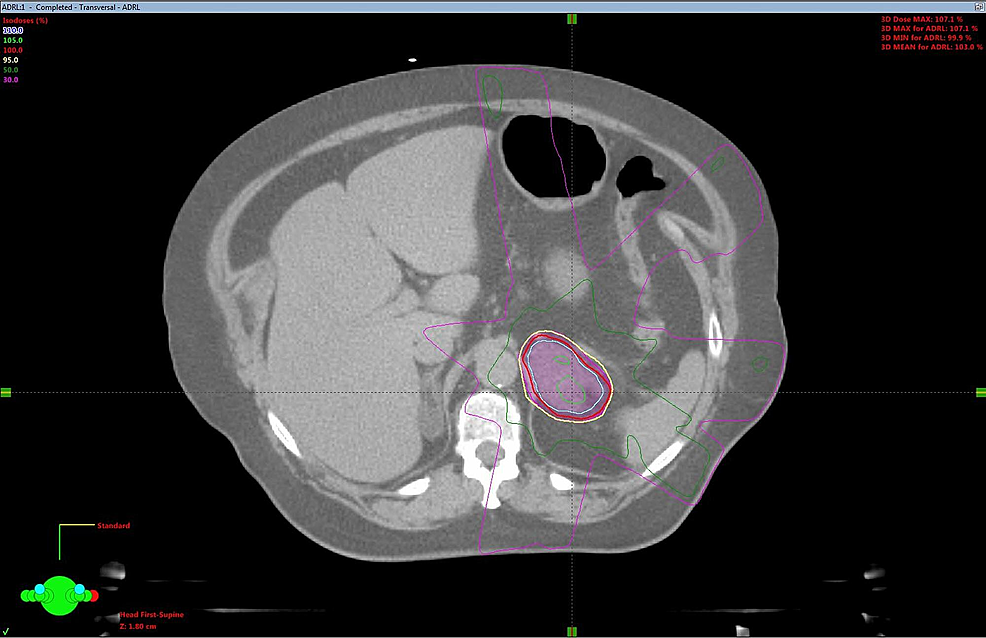

SBRT treatment planning CT scans can be seen in Figures 2-5. The left adrenal mass was treated first in June 2012 followed by the right lung mass one month later. 4D CT simulation with abdominal compression was performed for each site. Cone-beam CT image guidance was used prior to each fraction.

A dose of 30 Gy over six fractions was delivered via linear accelerator to the left adrenal mass utilizing a five-field intensity-modulated radiation therapy (IMRT) technique with six MV photons, to a prescribed isodose of 100%. The right lung mass was treated with a nine-field non-coplanar SBRT technique with a dose of 48 Gy in four fractions over two weeks, prescribed to the 80% isodoses. Treatment concluded in August 2012. Treatment was well tolerated, with a short bout of nausea reported.